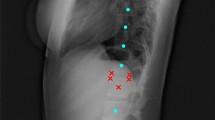

An example of the step by step model for landmarks prediction on a representative radiograph is reported in Fig. 1: in step I (CNN 1 + CNN 2), the original image is processed to obtain a heatmap representation of the localization of the first landmarks for all the visible vertebrae. The obtained coordinates are then used, in step II, for cropping the single vertebra and obtaining the corresponding representation as heatmap, thus allowing refining landmarks prediction. Finally, the position of the vertebral corners in the original image is calculated by means of geometrical transformations. The advantage of such an approach can be verified by observing the progressive refinement in the identification of the position of vertebral corners, which although acceptable in many cases by step I (see vertebrae from L2 to S1 in Fig. 1) improves evidently after applying the subsequent step 2 (see L1 and T12). Therefore, quantitatively, we can observe an improvement of the weighted mean of the median errors from 2.20 to 1.98% and from 2.04 to 1.68% for x and y coordinates respectively (see Table 1). The model performed well both when processing images with the region of interest in the foreground and with cases with black edges filling large portions of the image (Fig. 2). In some cases, the model missed the identification of some vertebrae or cannot recognize their correct position (Figs. 2, 3, 4). However, it is worth noting that in many of these cases, understanding where the vertebrae are located would be difficult even for an expert human observer (Fig. 4).

Predictions of the 2-step model for a representative image. The image from the test set is input into the model and processed to obtain an image fully annotated with the corners and names of the vertebrae. The heatmaps were generated using the Matplotlib library (https://matplotlib.org/) in Python 3.8 (https://www.python.org/downloads/release/python-380/).